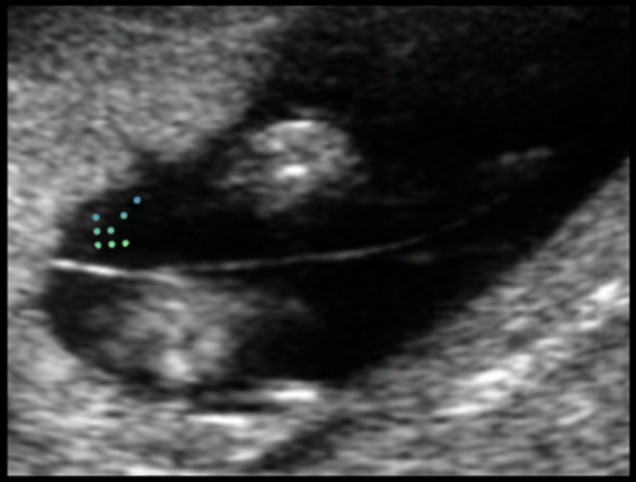

USG obstétrico

Qual é o sinal ecográfico apresentado na seta e o que indica?

Sinal do T

Presentes em gestações monocoriônicas

- Pode ser identificado até início do 2º TRI. Após esse período, caso a corionicidade não possa ser definida, a gestação deverá ser seguida como monocoriônica.

LEMBRAR que em gestações monocoriônicas, é necessário investigar síndrome da transfusão feto-fetal com ultrassonografia a cada 15 dias